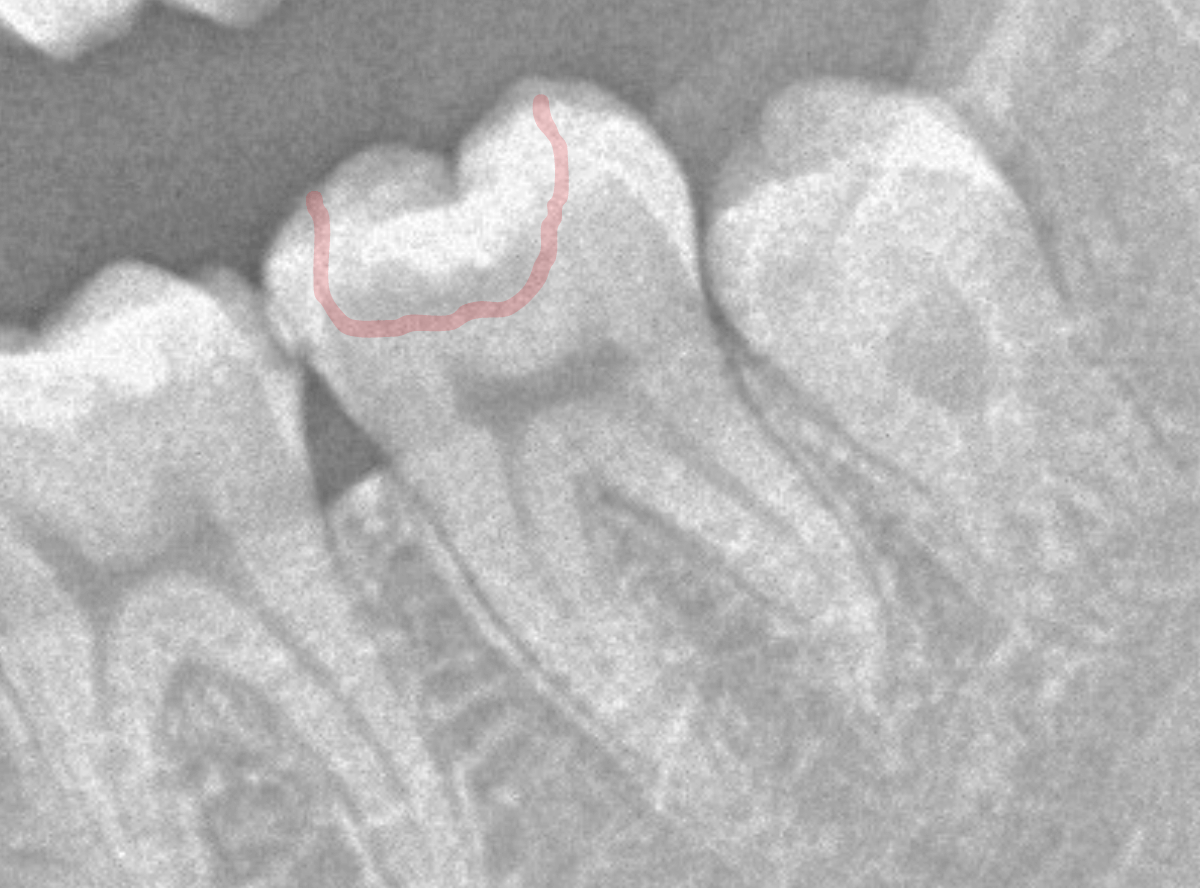

レントゲン写真を撮影しました。

青い線が神経

黄色い線がレジン

赤い線が虫歯

です。

思ったよりも深い虫歯をレジンで埋めてあったようで、さらにその中が虫歯になっている状況です。

神経までかなり近い虫歯と思われます。